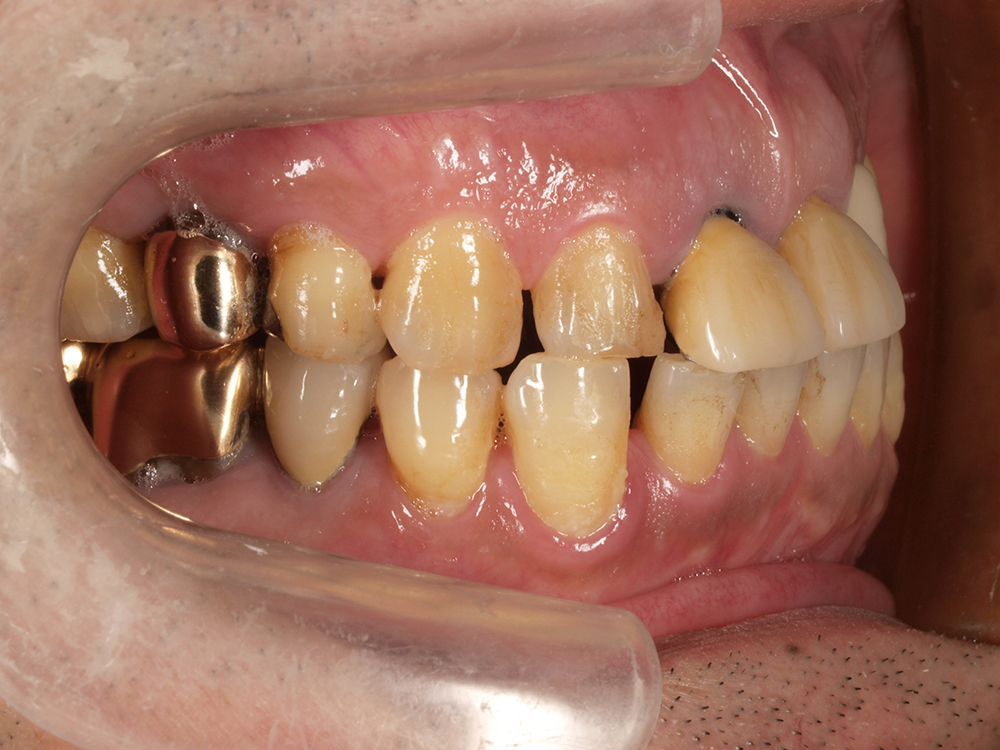

55歳 男性

- 主訴

- 前歯でしか咬めなく、食事を採るのに非常に困難で辛い

- 処置内容

- 上顎6本、下顎3本

- 治療費用

- 上顎:約230万(税込)下顎:約120万(税込)

- 治療期間

- 上顎:1年(仮歯まで8か月)下顎:8か月(仮歯まで5か月)

- リスク

- 上部構造物、仮歯の破折、術後の腫れ(3日)、人工歯根脱落リスクがあります